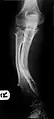

The diagnosis of HMO is based upon establishing an accurate correlation between the above-mentioned clinical features and the characteristic radiographic features. Family history can provide an important clue to the diagnosis. This is supplemented by testing for the two genes in which pathogenic variants are known to cause HMO namely EXT1 and EXT2. A combination of sequence analysis and deletion analysis of the entire coding regions of both EXT1 and EXT2 detects pathogenic variants in 70–95% of affected individuals.[3][4] The hallmark of radiographic diagnosis is the presence of osteochondromas at the metaphyseal ends of long bones in which the cortex and medulla of the osteochondroma represent a continuous extension of the host bone. This is readily demonstrable in radiographs of the knees.[3][1]

Multiple osteochondromas causing deformity of the forearm (shortening of the Radius with secondary bowing of the Ulna).